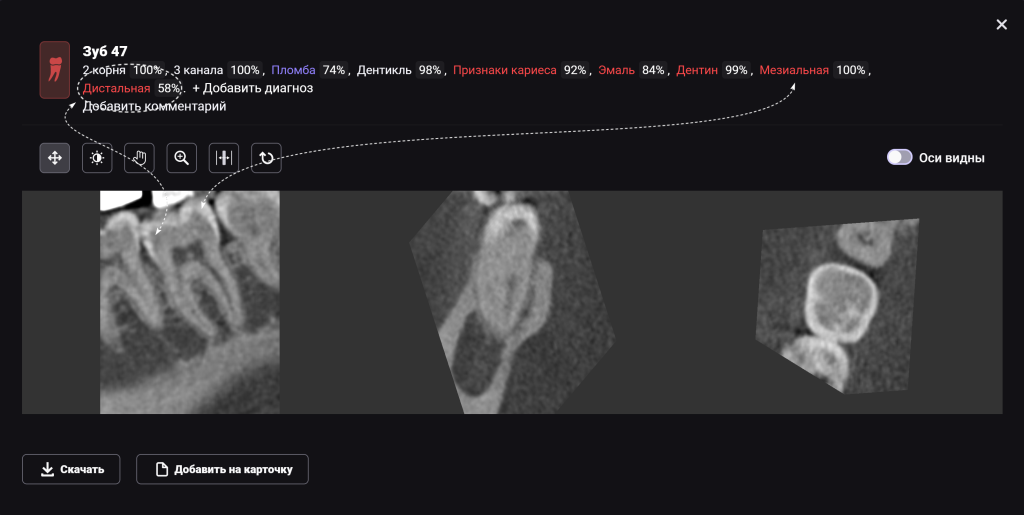

Клинически подтверждено наличие кариеса на дистальной и мезиальной поверхностях зуба 4.7